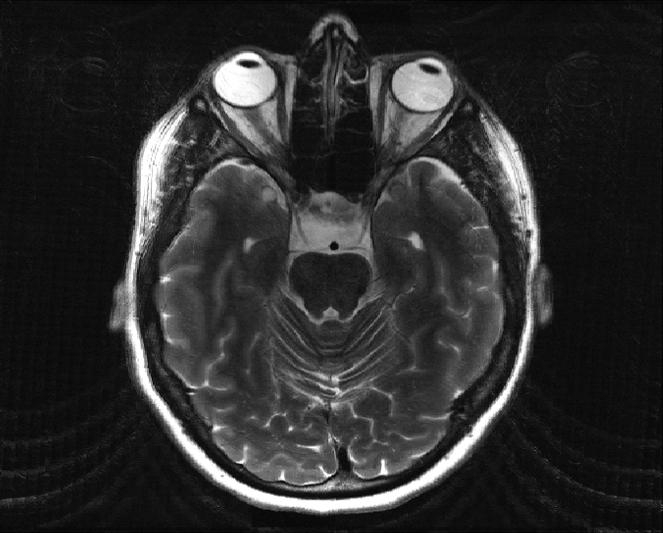

Dabrowski1,2, Martin Ndengera3, Felix T. Kurz1,4, Frédéric Grouiller1,2,3, et Sébastien Courvoisier1,2

Le mouvements en IRM contexte et solutions

L’IRM, technique d’imagerie médicale non invasive, est très sensible aux mouvements du patient car l’acquisition spatiale se fait de manière ségmentée. L’information complète requiert une séquence longue. En effet, l’IRM ne fait pas directement une image comme en rayon-X (RX ou CT-scan). En IRM, Le signal de résonance magnétique mesuré est enregistrée dans l’espace des fréquences spatiales appelé “espace-K”. L’image finale utilisée par les radiologue est obtenue par “reconstruction” via une transformation mathématique, la transformée de Fourier.

SISMIK le modèle de correction

Nous proposons un système de correction de mouvement rétrospectif sur les données de mesure IRM (espace-K) appelé SISMIK qui reconstruit des images avec moins d’artéfacts de mouvements.

Le système est dit hybride entre l’intelligence artificielle et les méthode algorithmiques plus traditionnelles, combinant les avantages des deux approches.

1. Les mesures “brutes” sont montrées à un réseau de neurones convolutionnel (CNN) entraîné au préalable.

2. le CNN estime pour chaque ligne d’aquisition le déplacement relatif effectué par rapport au lignes adjacentes.

3. le réseau produit une trajectoire complètes (mouvement dans le temps) le long de l’acquisition

4. la trajectoire et les données brutes sont envoyées au second algorithme afin qu’il corrige et reconstruise les images correspondantes.

Notre méthode est dite rétrospective (appliquée après la mesure) et basée sur la technique IRM exclusivement. Ses avantages sont les suivants:

▪ Aucune modification des séquences cliniques usuelles (des modifications rendraient les séquences non-standard et nécessitent un développement et une validation spécifique pour chaque constructeur/marque IRM).

▪ Pas de séquence additionelle nécessaire, la référence du mouvement est relative et contenue dans l’acquisition

▪ Aucun équipement supplémentaire ou externe est nécessaire.

▪ Polyvalent au contrastes IRM (T1w, T2w démontré) et au contenu (théorique, à tester). C’est à dire que par exemple le réseau de neurone peut être entrainé sur des données IRM réalisé avec un contraste T1w acquis sur des objets comme des fruits mais appliqué à des cerveaux et en contrastes T2w